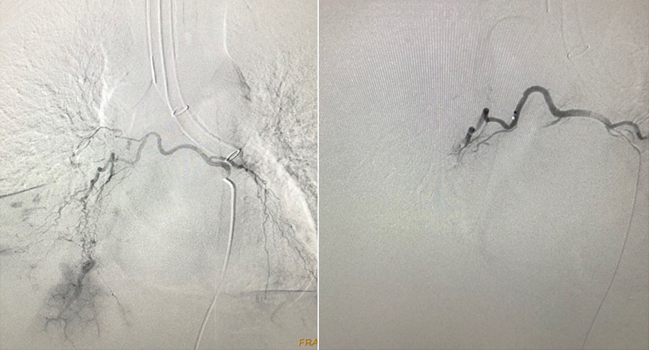

支气管动脉造影可见右下肺的支气管动脉有多处血管迂曲紊乱,远端可见片状显影区,并且可见支气管动脉-肺动脉瘘(图5)。置入微导管至右侧病变的支气管动脉中,在其中注入适量的明胶海绵颗粒进行栓塞。再次造影显示右侧支气管动脉远端原病变区没有显影。术后患者血红蛋白稳定,第三天复查气管镜,取出右中间段填塞的明胶海绵,最终患者顺利拔除气管插管,出院后随访1年未再出现咯血。

图片

图5  支气管动脉造影